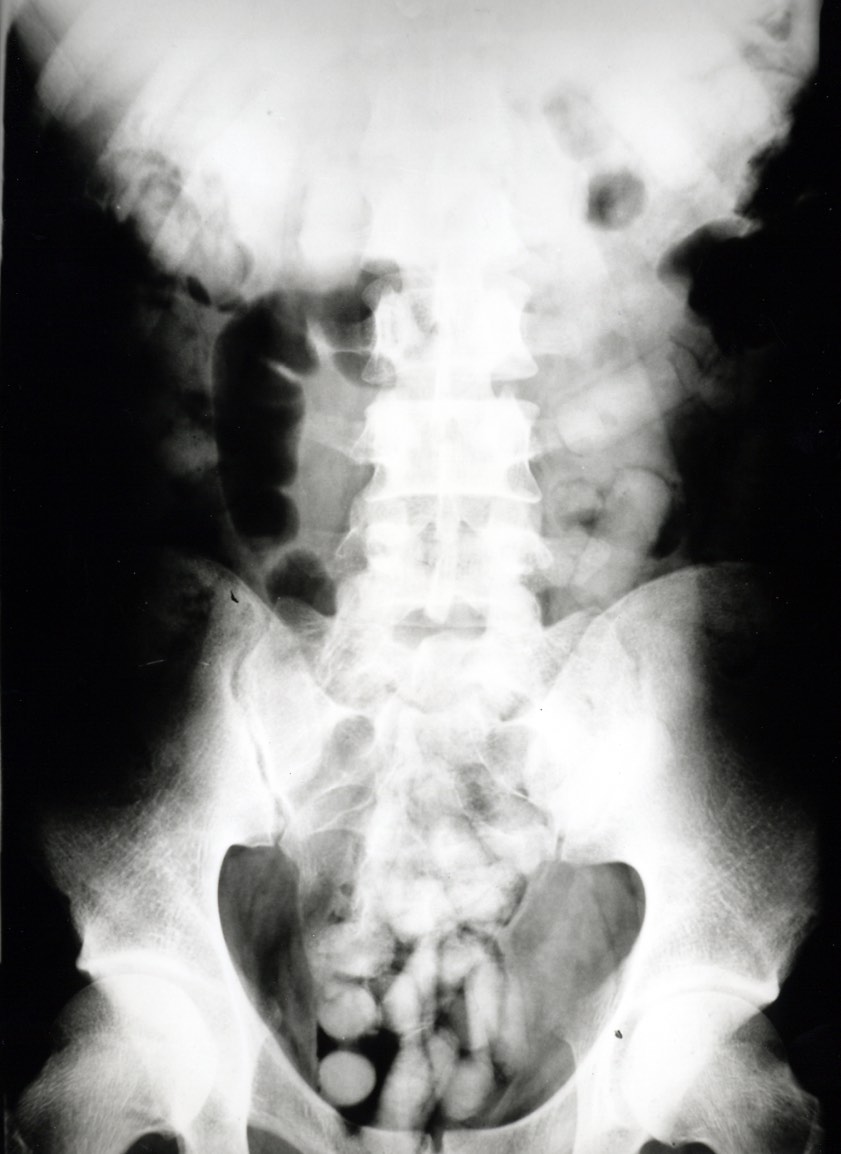

Rund ein Kilo der Droge hatte ein 26-jähriger Bodypacker verschluckt, als er den Münchner Zöllnern auffiel. Ein Röntgenbild brachte es ans Licht.

Bei der Zollkontrolle habe der junge Mann äußerst nervös gewirkt und sich zudem in Widersprüche verstrickt, was seine Auskünfte über Reisezweck und -dauer anging. Die Beamten führten daraufhin einen Drogenwischtest durch, der Kokain anzeigte. Da aber weder am Körper noch im Gepäck des 26-Jährigen Kokain gefunden worden war, musste der Mann im Krankenhaus geröntgt werden.

"Das Röntgenbild bestätigte den Verdacht der Zöllner. Im Laufe des Tages kamen 95 Behältnisse mit Kokain zum Vorschein, die über den natürlichen Weg ausgeschieden wurden", berichtet Marie Müller, die Pressesprecherin des Hauptzollamts München.